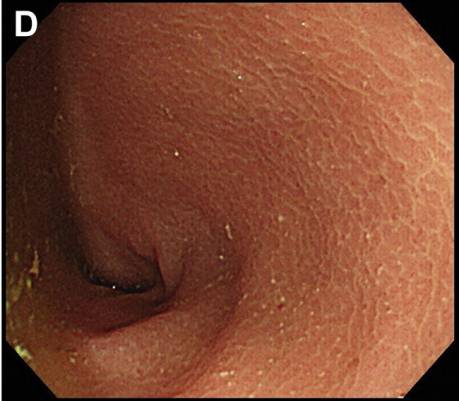

而下消化道内镜检查结果显示:白色小斑点样病灶贯穿结肠(图C,窄带成像),且直肠黏膜水肿(图D)。但是末端回肠未见明显异常。